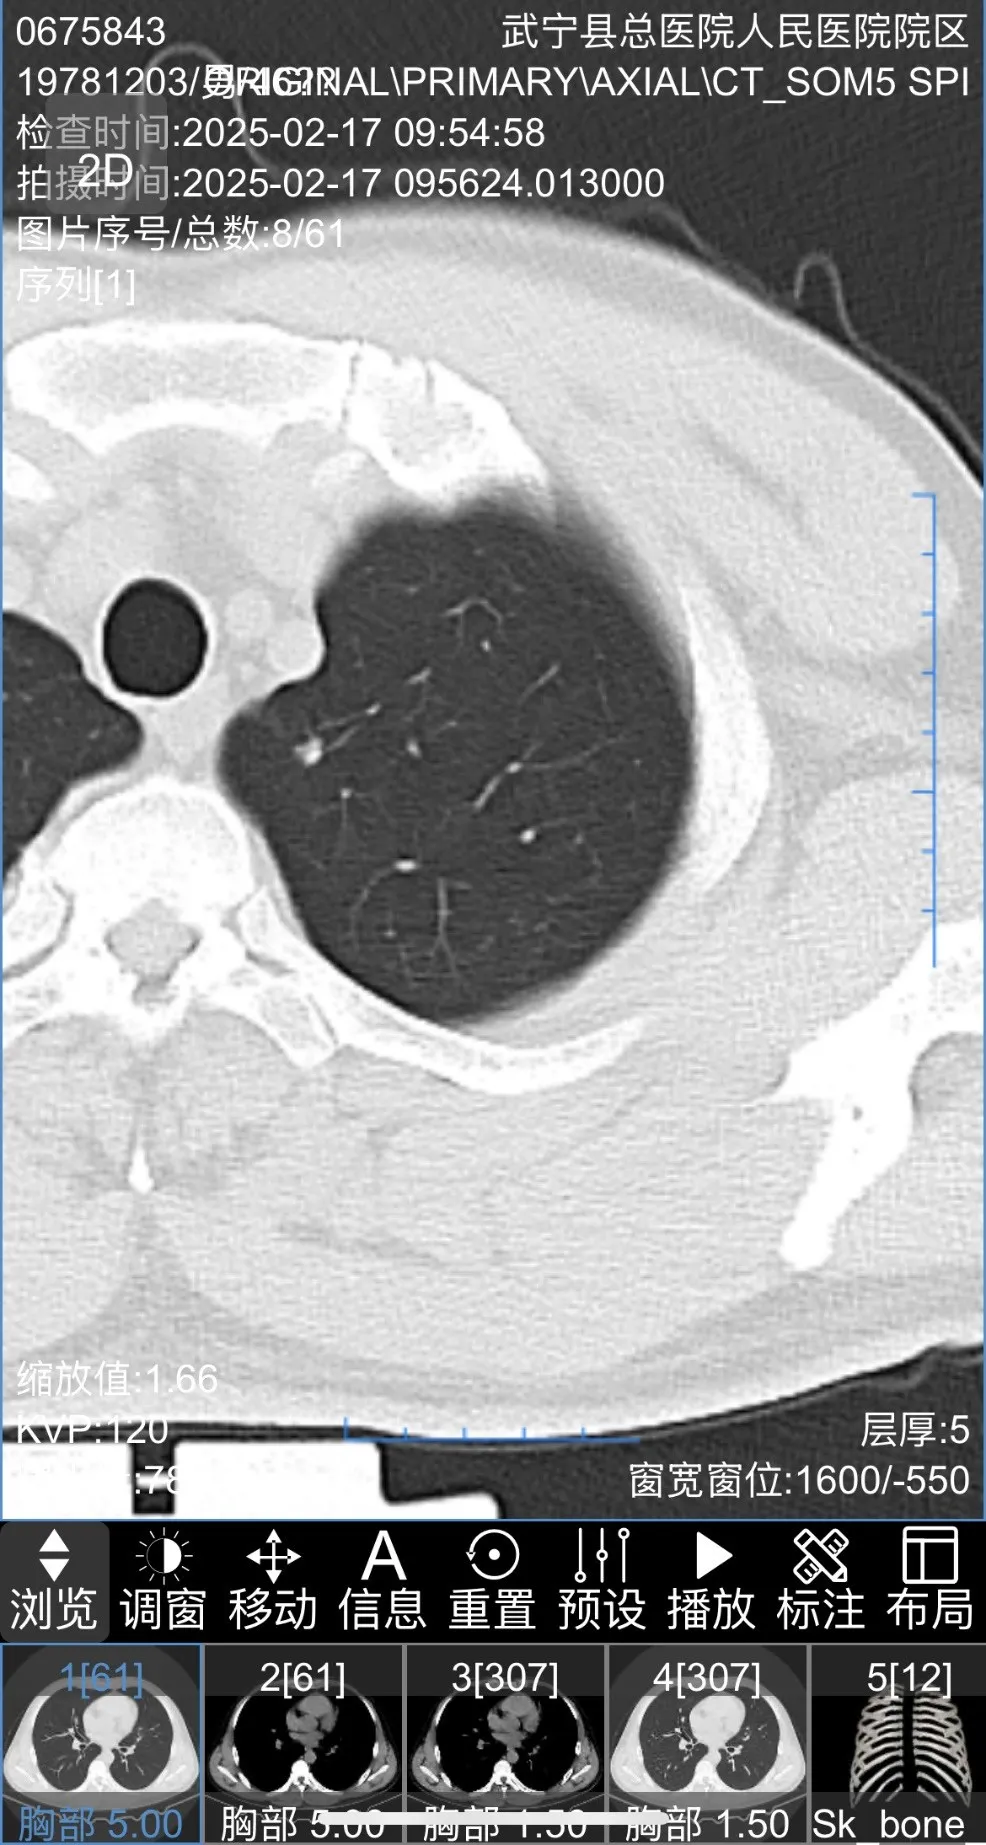

患者,仲某,48歲,診斷為左側上葉多發性肺結節入院,考慮早期(qī)肺癌(ái)。患者入院後,主治醫師徐亦熊了解患者病情後,因患者(zhě)較年輕,為多發性肺結節(jiē),盡可(kě)能切除肺結節,保留更多健康肺組織,提升患(huàn)者術後肺功能和生(shēng)活質量成為重中之重。

患者胸部(bù)CT圖片如下

最終為患者行左肺上葉S1+2c與S4a聯合亞段切除及S1+2a段(duàn)楔形切除術。患者術後2天出院,恢(huī)複良好,手術後對肺功能無影(yǐng)響。結節1病理為(wéi)原位癌,結(jié)節2為良好病灶。患者對91麻豆视频(men)手術方(fāng)案非(fēi)常滿意,痊(quán)愈出院。

三維重建輔助下肺癌精準肺段切除術,是一種先進的肺癌手術方式。主要(yào)借助CT影(yǐng)像數據,利(lì)用計(jì)算機技術對肺部、血管及支氣管等進行三維(wéi)立(lì)體建模,清晰呈現肺部解剖結構。優勢在於,醫生能精準定位腫瘤位置和(hé)邊界,規劃手(shǒu)術路徑,準確切除包含腫瘤的肺段,保留更多健康肺組織(zhī),提升患者(zhě)術後(hòu)肺功能和生活質量。同時減少術中出血(xuè)、降低損傷周圍組織風險。